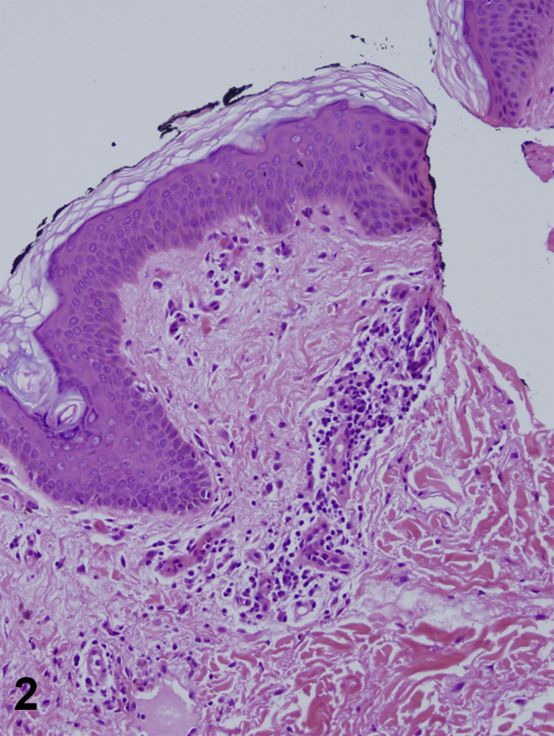

一名39岁妇女,有2周新发双侧腿部疼痛、关节痛和卧床史。此外,患者诉有2天的右膝、右侧腿部、后颈和头皮瘙痒皮疹病史,以及3天的咽喉疼痛和发烧史(每日最高温度39.4°C)。实验室值包括白细胞计数11.1,中性粒细胞90%;血小板469;铁蛋白3662 ;血沉115 ;c反应蛋白225;天冬氨酸氨基转移酶91;丙氨酸氨基转移酶67;抗核抗体(ANA)和类风湿因子阴性。体格检查发现有剥落、线状、界限不清的紫色丘疹和斑块(图1)。侧翼活检显示交界性皮炎(图2和图3)。

图2